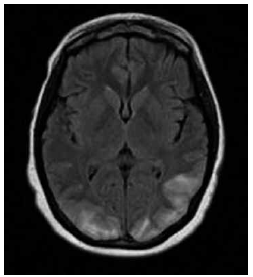

Garota de 13 anos de idade com diagnóstico recente de insuficiência renal crônica apresenta episódio de cefaleia, turvação visual e crise epiléptica tônico-clônica generalizada. A pressão arterial é de 180 x 100 mmHg. A ressonância magnética de crânio demonstra o achado a seguir.

O diagnóstico mais provável é